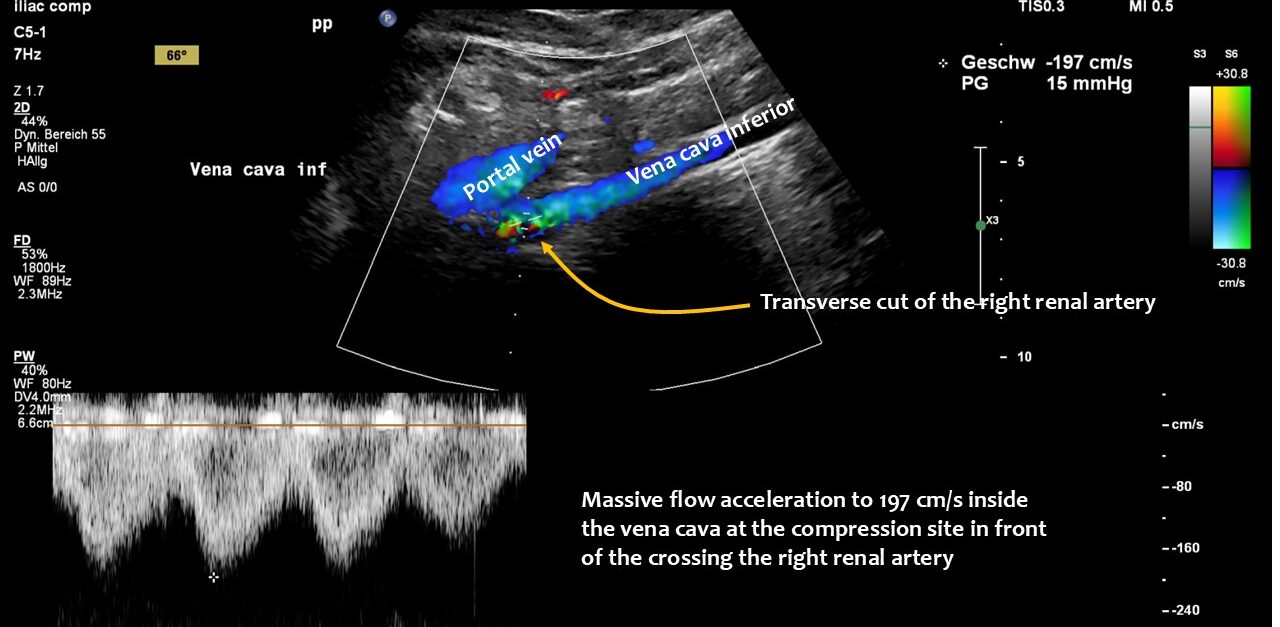

However, functional colour Doppler ultrasound revealed that the problems were caused by compression of the inferior vena cava. The patient’s increased lumbar lordosis, resulting from a connective tissue disorder (hypermobile Ehlers-Danlos syndrome), pushed the inferior vena cava ventrally.

The upper lumbar vertebrae thus acted as a barrier against which the expanding duodenum pressed the vena cava. The situation was exacerbated by the duodenum not functioning properly, causing food to become lodged in the descending portion of the duodenum, directly in front of the inferior vena cava.

Due to the lax connective tissue, the liver was less fixed and thus developed orthostatic hepatoptosis, sliding down like a sled on a ramp — the cranial slope of the lumbar lordotic curvature — while standing. This compression was exacerbated by the perpendicular crossing of the right renal artery, which runs behind the vena cava and in front of the lumbar spine, acting as a bar and making the compression even more efficient.